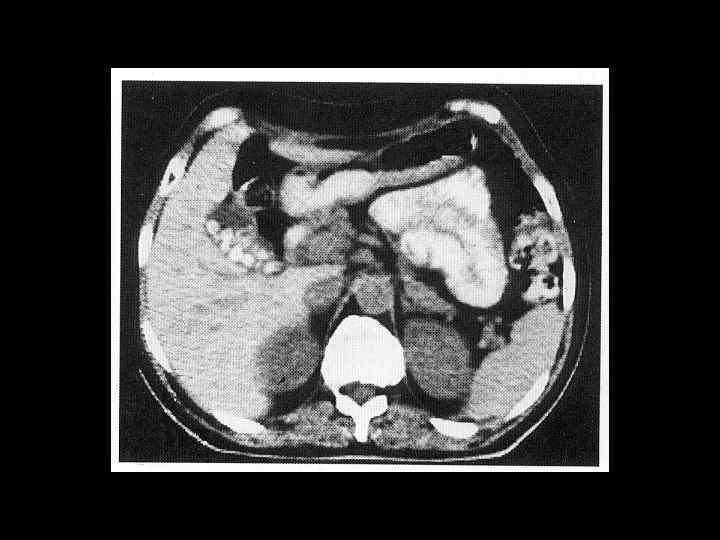

АКТУАЛЬНЫЕ ВОПРОСЫ РЕНТГЕНОЛОГИИ ЛУЧЕВАЯ ДИАГНОСТИКА ЗАБОЛЕВАНИЙ ЖЕЛЧЕВЫДЕЛИТЕЛЬНОЙ СИСТЕМЫ Желчекаменная болезнь КТ семиотика